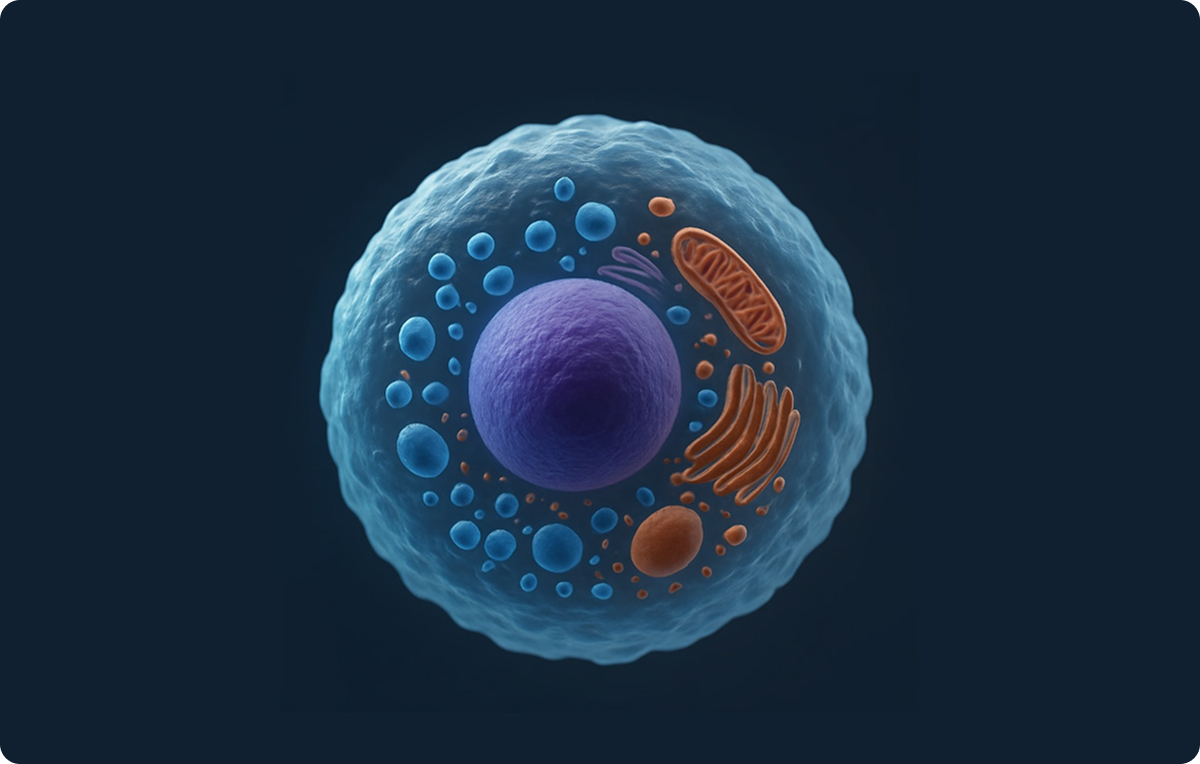

幹細胞と再生医療

- 幹細胞は、様々な組織に分化できる能力を持つ特別な細胞。

- 皮膚、骨、血液など、体内の多様な組織を構成し、日々新しい細胞へと置き換えられる。

- 幹細胞は、骨、脂肪、歯髄、臍帯血などから採取可能。

- これらの幹細胞を活用して病気を治療するのが「再生医療」である。